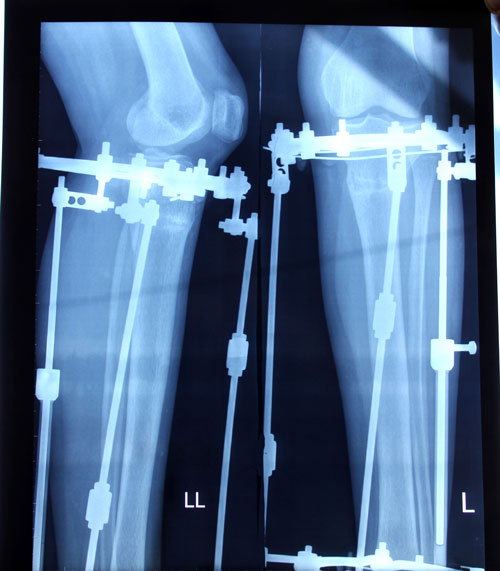

Рентген в 60 дней.

Рентген в 90 дней.

Приезжайте на снятие аппаратов!